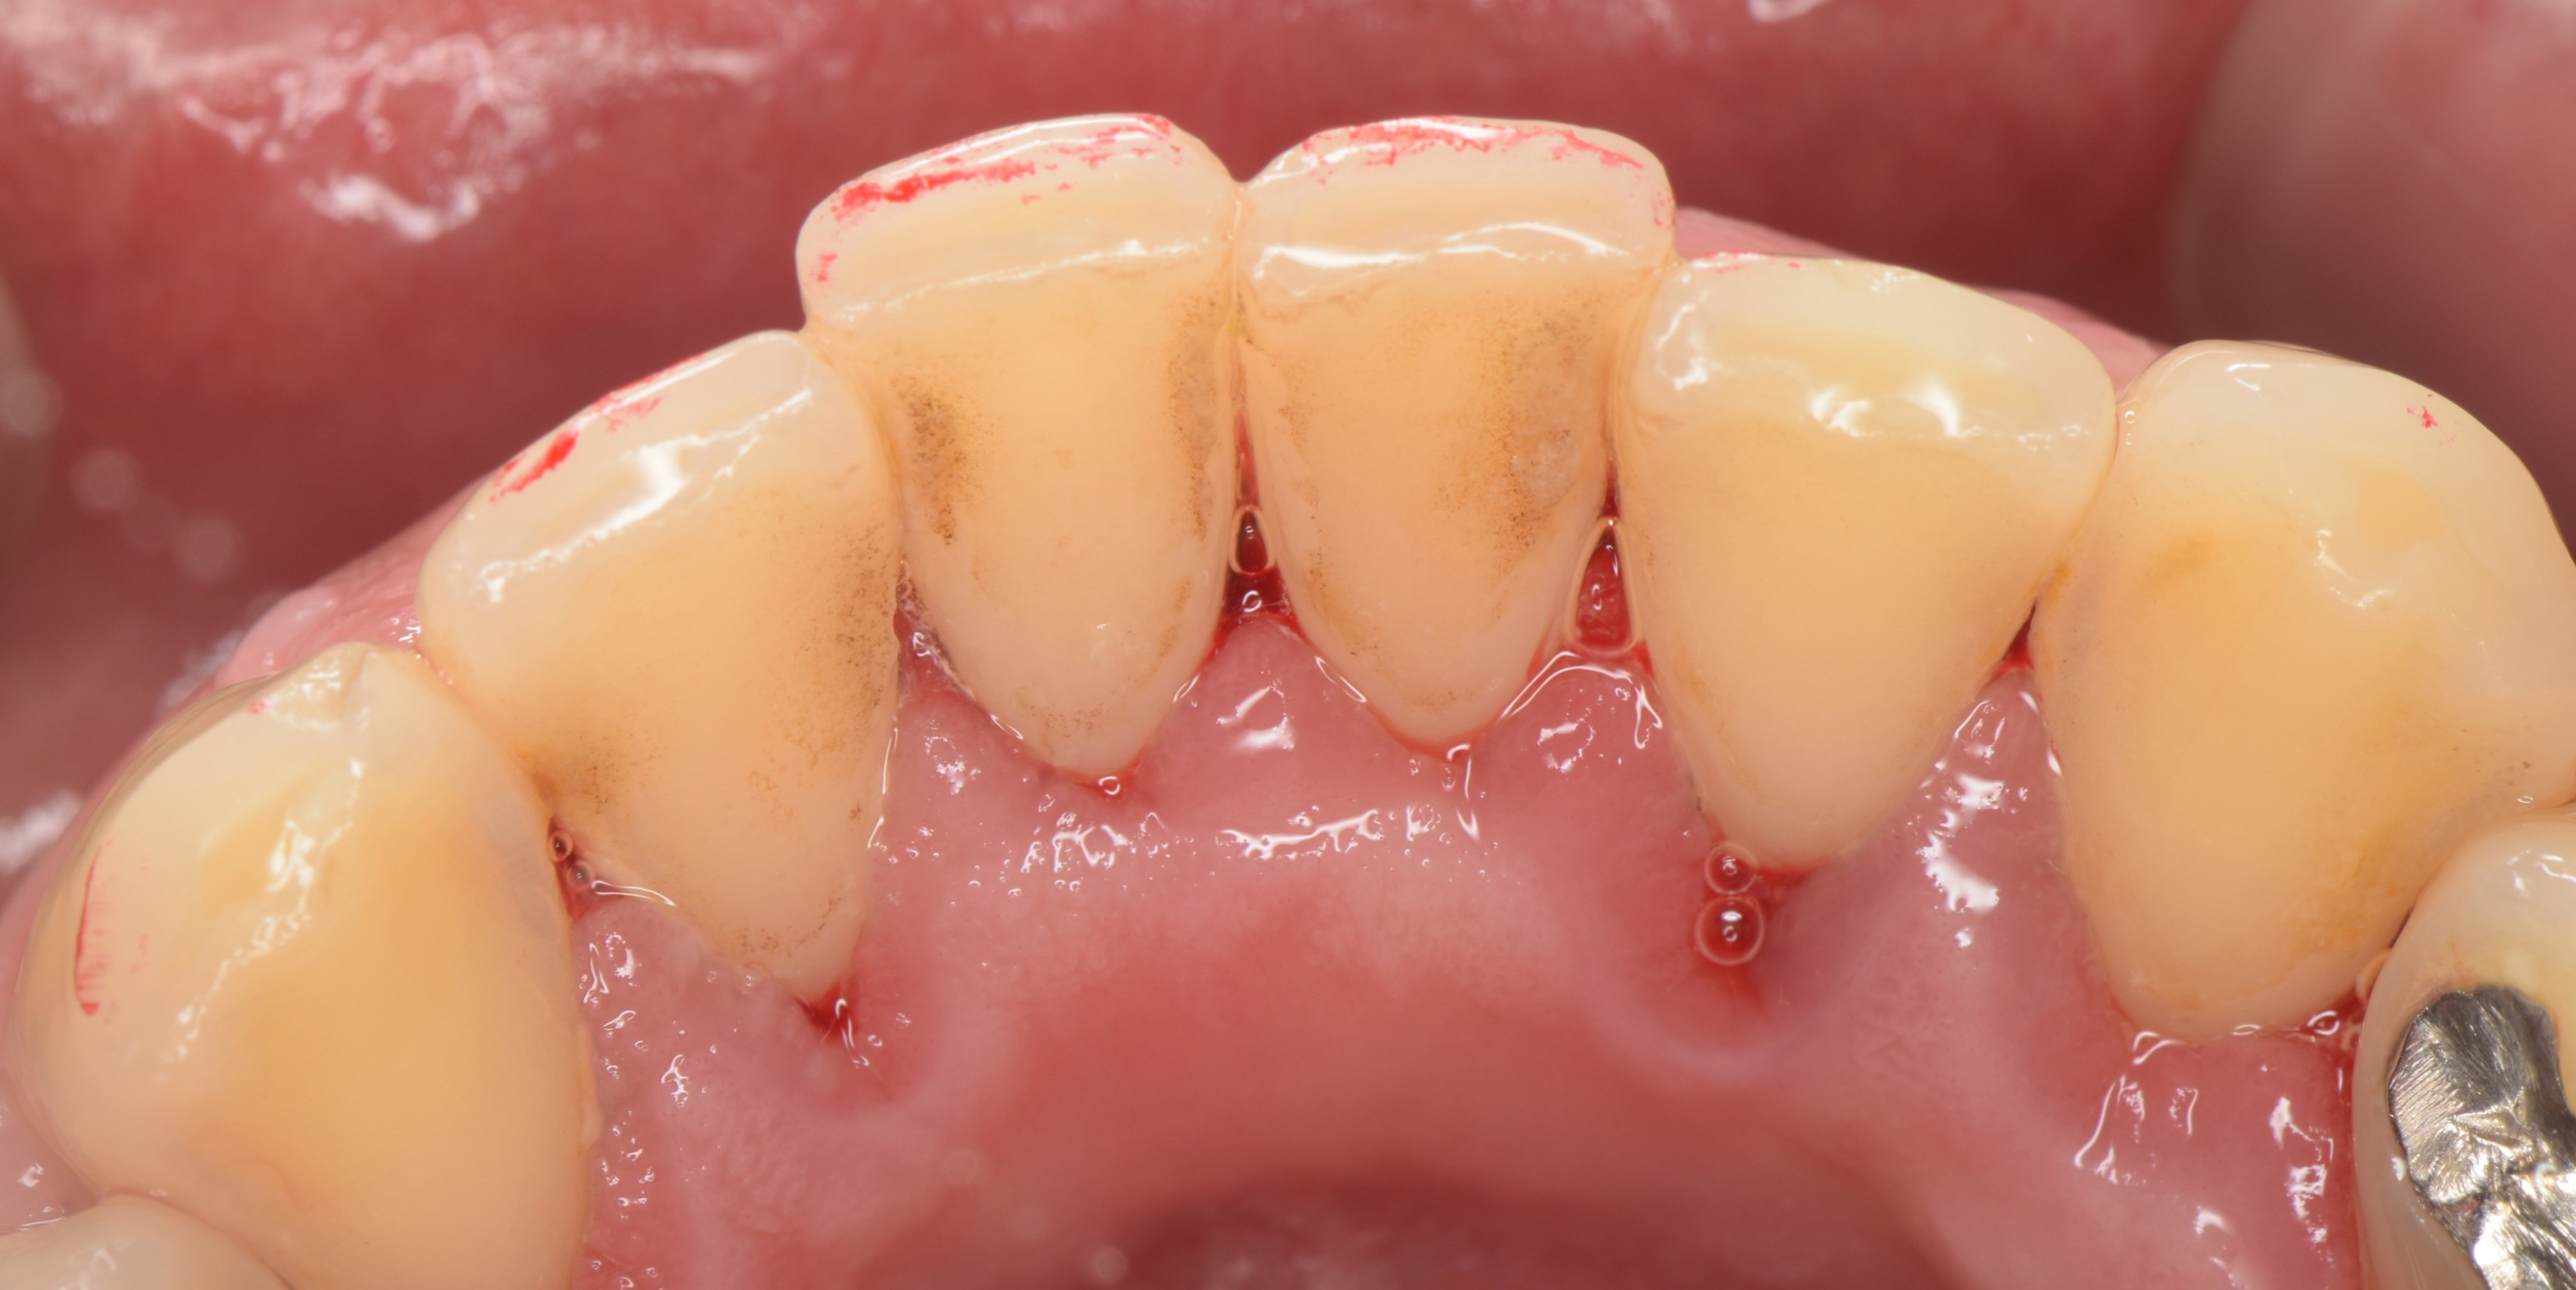

歯石の除去直後の状態

歯石に隠れていた歯肉が見えるようになりました。

歯石と接していた歯肉が赤く腫れているのが見てとれます。

炎症も進行してしまいますので、この状態になる前に定期的な検診を受けてほしいっす!